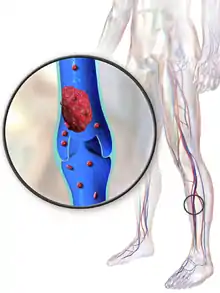

Deep vein thrombosis (DVT) is the formation of a blood clot in a deep vein, most commonly in the legs or pelvis.[8][lower-alpha 1] Symptoms can include pain, swelling, redness, and enlarged veins in the affected area, but some DVTs have no symptoms.[1] The most common life-threatening concern with DVT is the potential for a clot (or multiple clots) to detach, travel through the right side of the heart, and become stuck in arteries that supply blood to the lungs. This is called pulmonary embolism (PE). Both DVT and PE are considered as part of the same overall disease process, which is called venous thromboembolism (VTE). VTE can occur as an isolated DVT or as PE with or without DVT.[3] The most frequent long-term complication is post-thrombotic syndrome, which can cause pain, swelling, a sensation of heaviness, itching, and in severe cases, ulcers.[5] Also, recurrent VTE occurs in about 30% of those in the ten years following an initial VTE.[3]

An ultrasound with a blood clot visible in the left common femoral vein. (The common femoral vein is distal to the external iliac vein.)